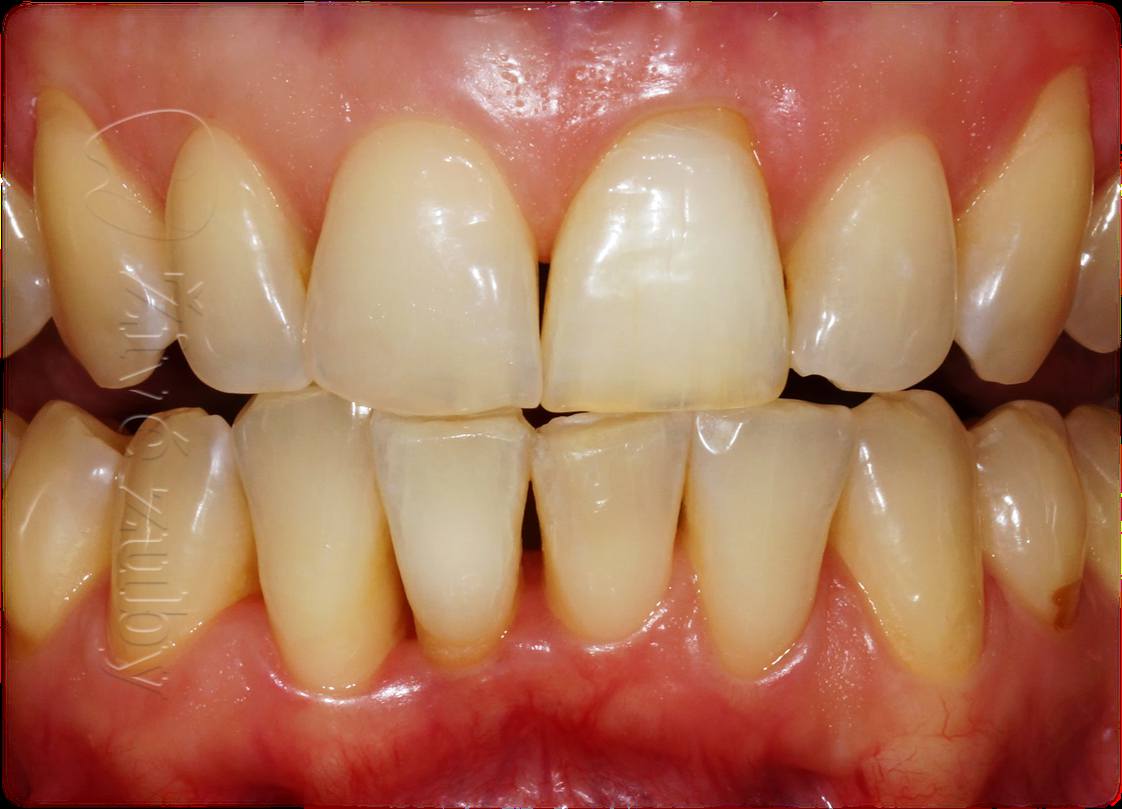

Mikroabraze a Infiltrace skloviny

(Ošetření Fluorózy a podobných lézí, demineralizaci skloviny, …)

Výchozí stav  ——- Kontrola po 2 letech